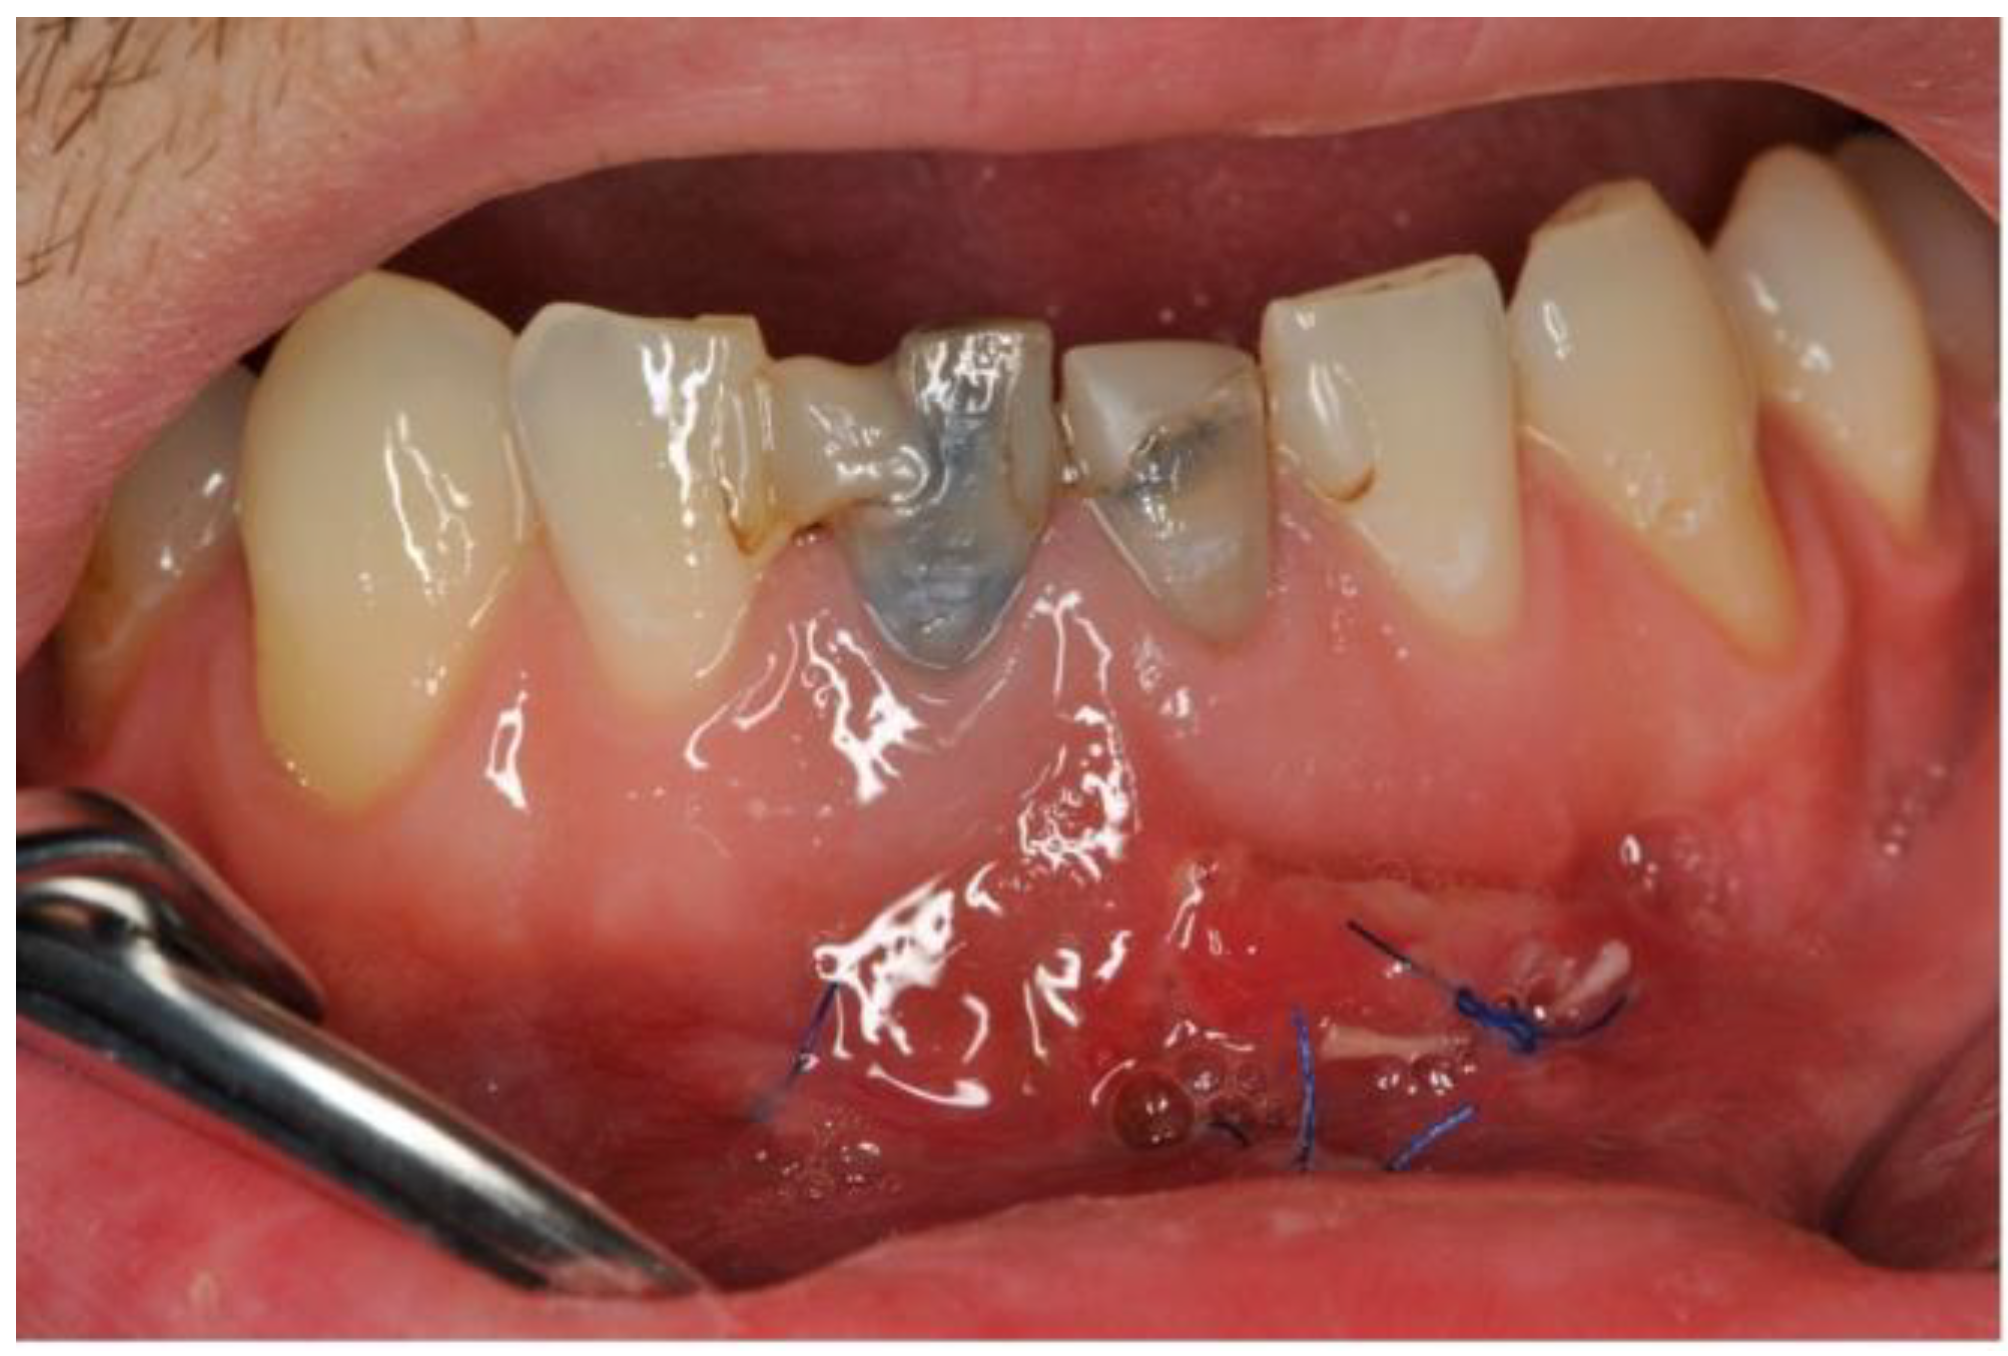

3. Clinical Procedure and Outcome